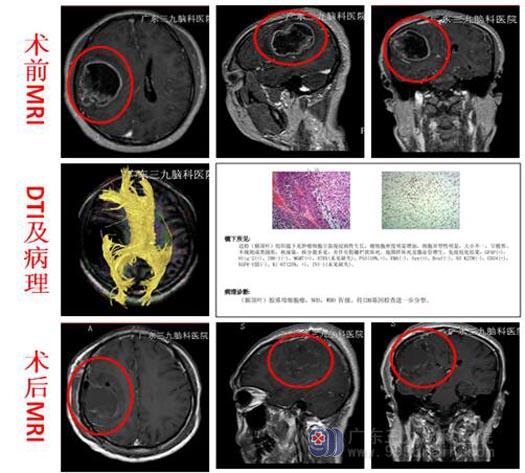

转至广东三九脑科医院综合神经外科,头颅MR提示:1.右侧额顶叶占位性病变,大小约4.8cm×5.9cm×4.7cm,考虑高级别胶质瘤,胶质母细胞瘤可能;2.右侧大脑镰下疝;3.双侧筛窦炎症;4.DTT(白质纤维束三维重建)检查,右侧额顶叶病变区纤维束中断、明显减少;右侧皮质脊髓束、胼胝体束右侧受压左移,右侧枕额束及右侧扣带束较对侧稀疏。因患者基础疾病多,待全面评估后再行手术治疗。

完善相关检查、排除手术禁忌症后,在唤醒麻醉下行“右侧额顶叶占位病变切除术”。术前导航定位、术中唤醒患者、电生理监测运动中枢,避开上下肢运动区,放射状切开硬脑膜,见皮层下肿瘤呈胶冻状,血供丰富,显微镜下将肿瘤分块全切除,术腔严格止血,手术顺利。术后病理:胶质母细胞瘤,NOS,WHO IV级。